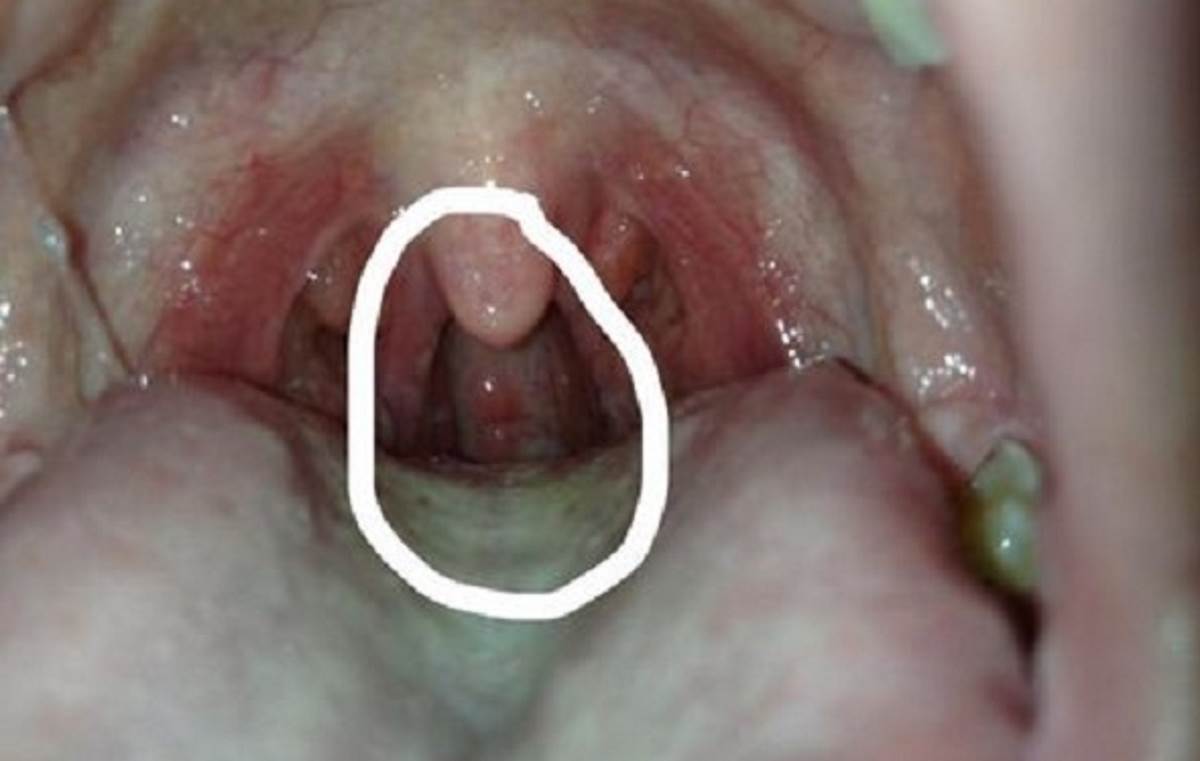

Главная Герпес Герпес в горле Симптомы герпеса горла

Симптомы герпеса горла

Полный размер 1200 × 761 пикселей Герпес в горле